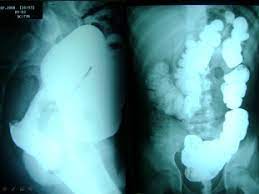

Many of the early signs and symptoms of cancer in children can also be caused by common illnesses or injuries, making childhood cancer hard to recognise and difficult to diagnose. Signs and symptoms of childhood colorectal cancer usually depend on where the tumor forms. Intestinal obstruction is a blockage that keeps food or liquid from passing through your small intestine or large intestine (colon). The tests are the only way to spot early cancer. Symptoms signs and symptoms of colon cancer include:

Intestinal obstruction is a blockage that keeps food or liquid from passing through your small intestine or large intestine (colon). Stomach pains are a very common complaint in little ones and are usually caused by noncancerous, benign conditions such as diarrhea or constipation, gastrointestinal viruses, or stomach upset from trying a new food. When a child has colorectal cancer, they may not experience any symptoms. The tests are the only way to spot early cancer. Check with your child's doctor if your child has any of the following: Regular screening tests for cancer of the colon or rectum, especially with a colonoscopy, is recommended as part of a health plan for those over. The annual incidence of cancer in children who live in developed countries is between 105 and 150 cases per 1 million children,1 making it the second leading cause of childhood mortality after. In children with acute myeloid leukemia (aml), leukemia cells may spread to the gums, causing swelling, pain, and bleeding. Bowel obstruction, also called intestinal obstruction, is a partial or complete blockage of the small or large intestine that results in food or fecal matter being unable to move through the intestines. What are the signs and symptoms of pediatric colorectal cancer? It is sometimes called colorectal cancer. Here are five of the most common, with tips on when to pick up the phone. Colorectal cancer may cause any of the following signs and symptoms.

Bowel obstruction, also called intestinal obstruction, is a partial or complete blockage of the small or large intestine that results in food or fecal matter being unable to move through the intestines.